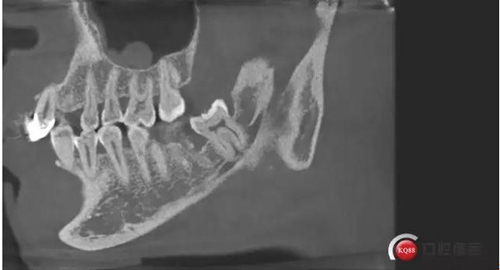

下面?zhèn)惹忻?/p>

1500632972_273609.jpg